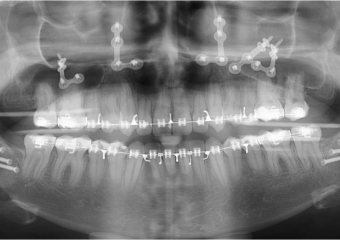

Raio x inicial